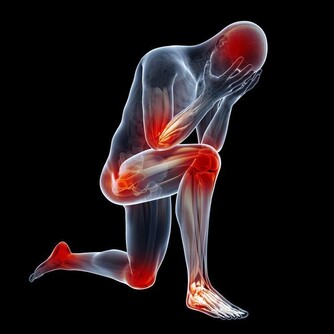

現代人長時間使用電腦、手機,或是維持不良姿勢,導致肩膀與頸部痠痛的問題越來越普遍。這種疼痛不僅影響日常生活,還可能導致長期的不適,甚至發展成慢性疼痛。本文將詳細探討肩膀與頸部痠痛的主要原因,並提供有效的預防與治療方法,幫助您改善不適,維持健康的身體狀態。

肩膀與頸部痠痛的常見原因

1. 長時間維持不良姿勢

長時間維持不正確的姿勢,如低頭滑手機、久坐不動、彎腰駝背等,會讓肩頸肌肉長時間處於緊繃狀態,造成痠痛。例如,辦公族長時間使用電腦,若螢幕高度不適當,容易導致肩頸前傾,增加肌肉負擔,導致疼痛。